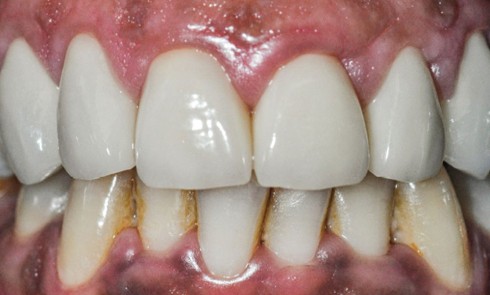

Article réservé à nos abonnés Approche clinique moderne d’une patiente atteinte d’usure érosive

Le diagnostic préalable de l’étiologie des phénomènes d’érosion-usure, qui peut être chimique, abrasive ou encore attritive, est essentiel pour permettre...